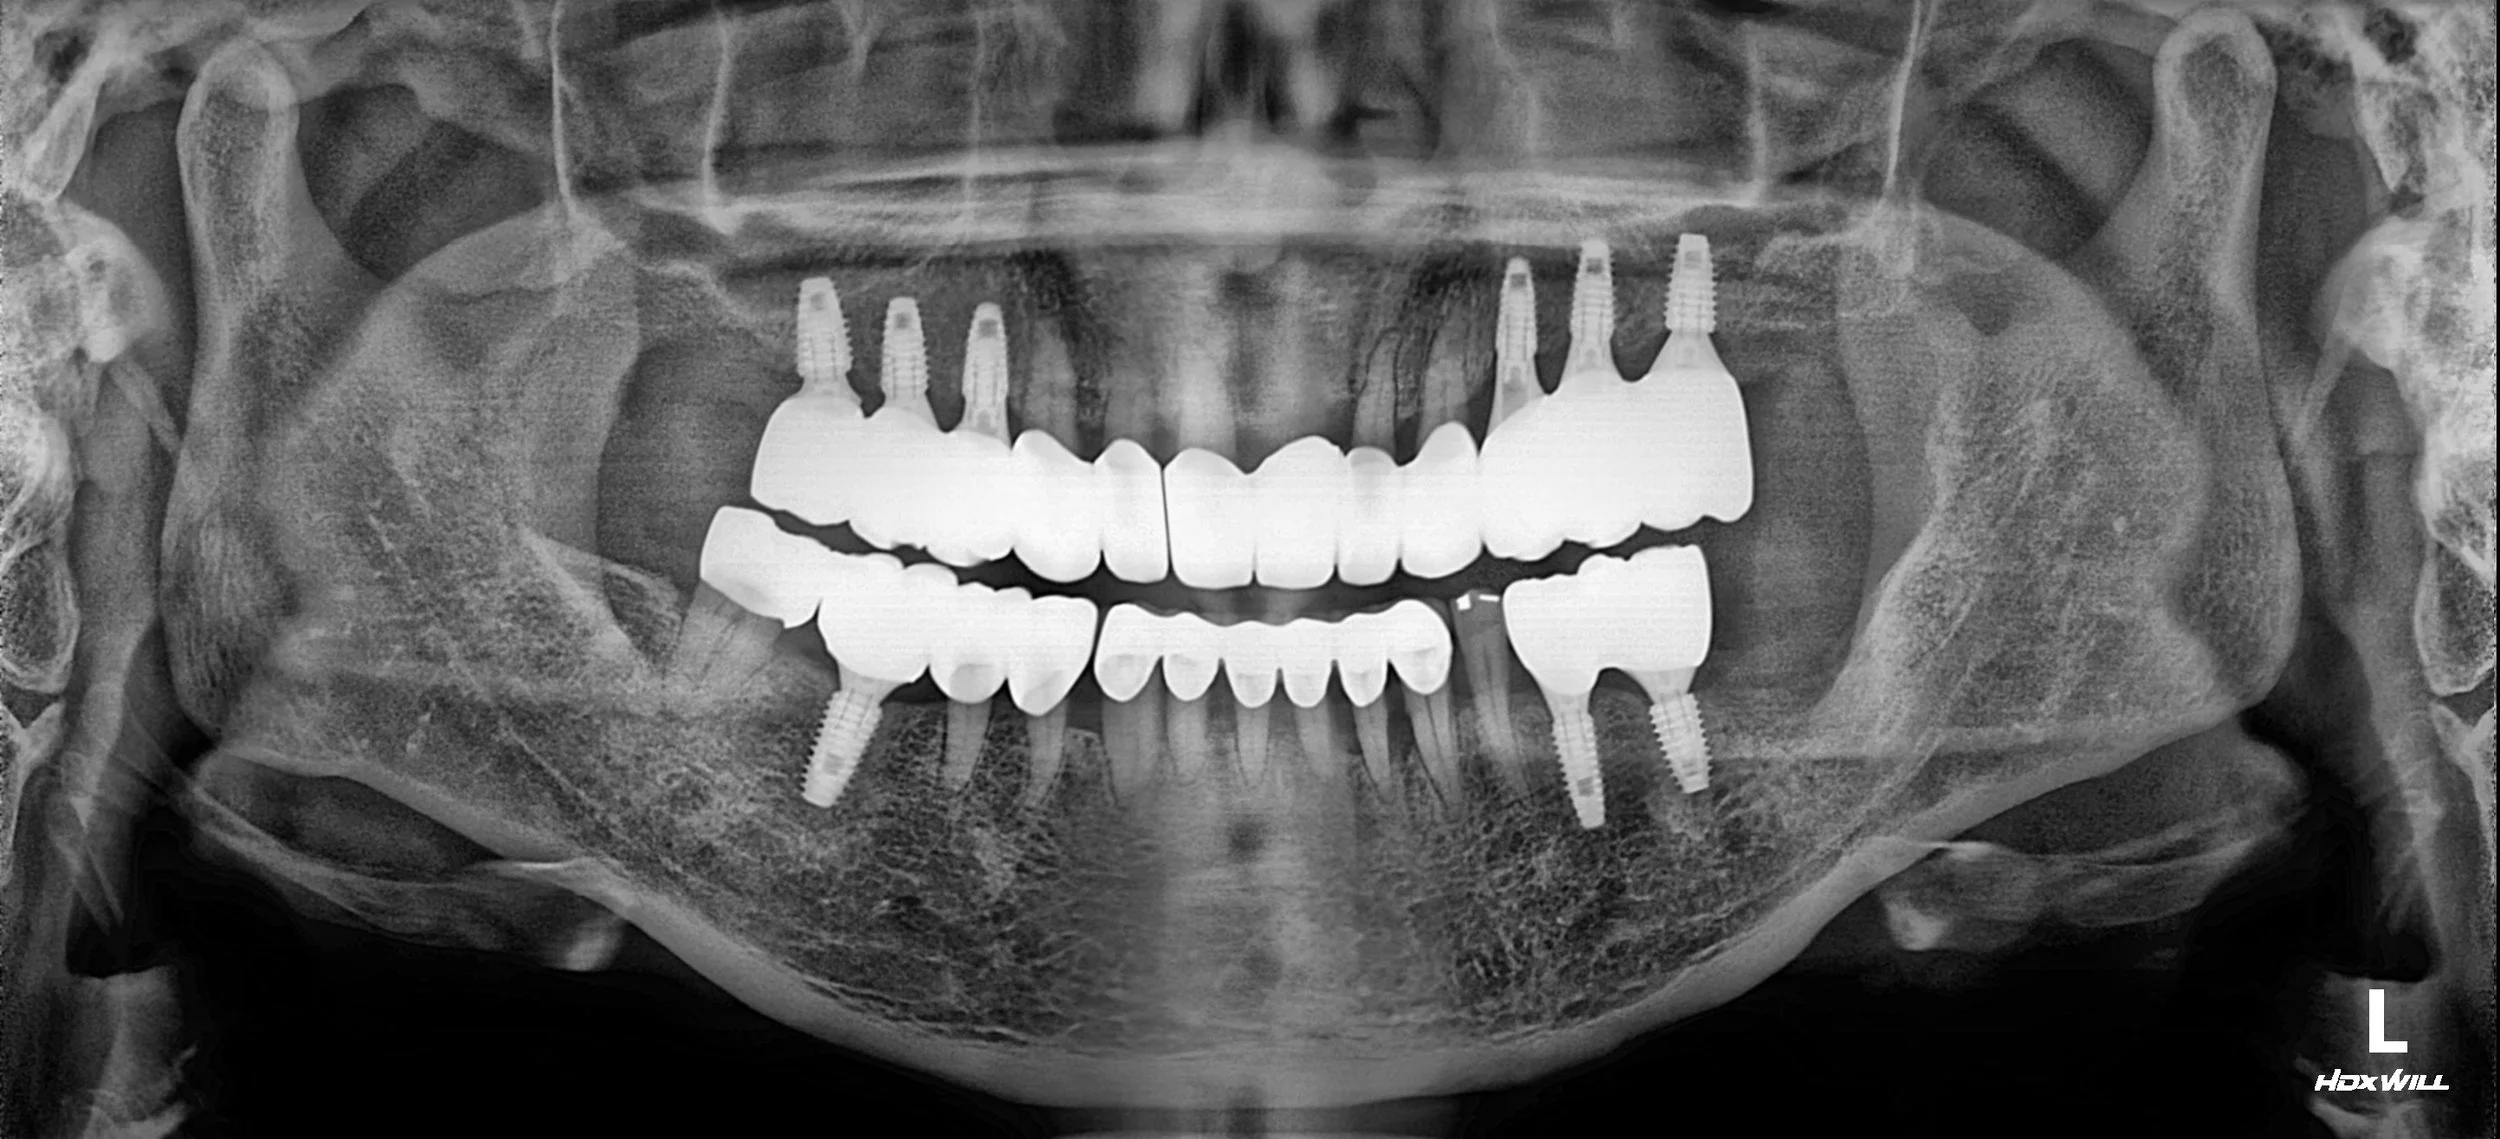

OPG - BEFORE